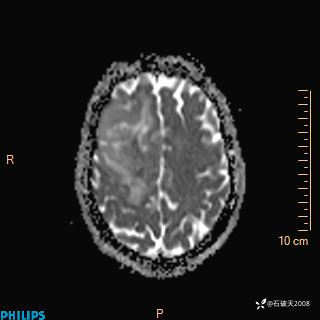

2024.2.21MR

ADC